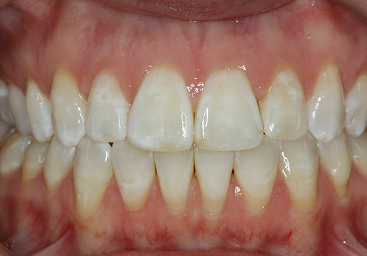

Deep bites are another common problem we see here and can lead to problems with gum tissue and wear of the teeth. This patient of ours was treated with our metal braces.